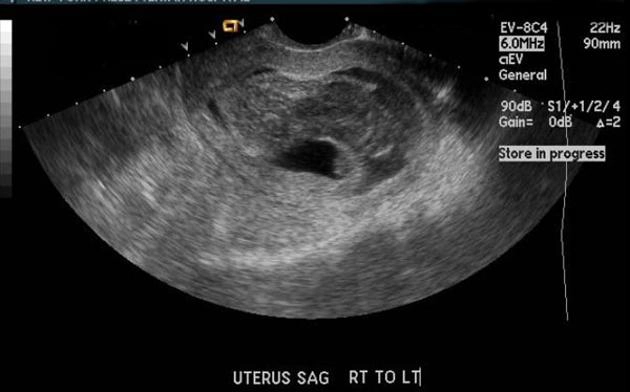

Tụ máu dưới màng nuôi (Tụ máu quanh túi thai)